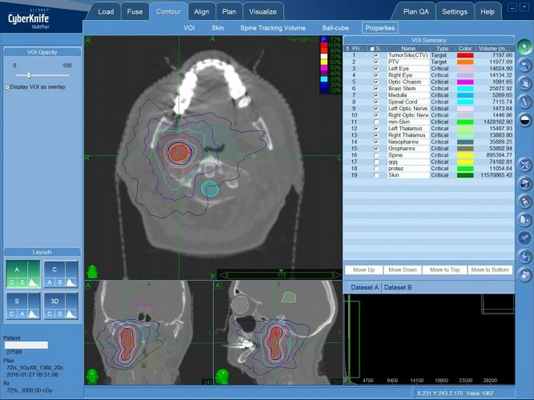

В зависимости от расположения, размера и типа невриномы, врач назначает оптимальный вид лечения. Наиболее часто пациента направляют на операцию. Однако, остановить рост опухоли неинвазивными методами, особенно при диагностике на ранних стадиях, стало возможным с развитием новых технологий лучевого лечения, таких как Кибер-Нож. При этом сохраняются функции рядом расположенных нервов, что крайне важно для сохранения качества жизни после лечения.

Лучевая терапия рекомендована, если операцию невозможно провести, или если пациент отказывается от неё. С внедрением в практику инновационной системы «КиберНож» появилась возможность неинвазивного, быстрого, сверхточного и комфортного лечения неврином любой локализации.

Лечение на системе КиберНож

Традиционным методом лечения параганглиом является тотальное удаление в процессе нейрохирургической операции. Однако особенность строения данной опухоли, включающей в себя множество кровеносных сосудов, не позволяет хирургам показывать низкую частоту послеоперационных осложнений. Именно поэтому радиохирургическое лечение на КиберНоже показывает большую эффективность при меньшем количестве осложнений.

Неправильная форма опухоли, увеличивающая объем удаляемых здоровых тканей при операции, не является препятствием для КиберНожа: множественные пучки формируют зону высокой дозы излучения точно в очертаниях опухоли, не вызывая повреждения здоровых структур мозга.

Первым этапом после определения тактики лечения становится создание пространственной модели опухоли, в которой будет сосредоточена доза ионизирующего излучения, которая будет доставлена точно в опухоль. После составляется план лечения — проводится расчет количества тонких одиночных пусков излучения высокой мощности и множественных позиций, с которых они будут направлены в зону опухолевого поражения. Практическая доставка излучения в опухоль будет проведена из различных положений мобильного линейного ускорителя, размещенного на роботизированном манипуляторе.

Безоперационное лечение параганглиомы на КиберНоже — план лечения